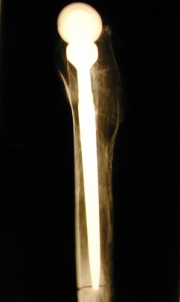

Bleibt diese Osseointegration über Jahre bestehen? Die folgenden Bilder illustrieren dies. Abb. 22a und b zeigen das Präparatröntgen einer 83-jährigen Patientin, welche 20,7 Jahre nach Implantation des Titaniumschaftes verstorben ist. Es finden sich stabile Verhältnisse. Die Abbildungen c und d zeigen, dass das Implantat (Ti) stabil im umgebenden Knochen verankert ist (Dünnschliffpräparate Prof. Dr. F. Lintner, Pathologie, Otto-Wagner-Spital). Dies bedeutet, dass die Osseointegration auch beim alten und sehr alten Menschen auch noch nach vielen Jahren funktioniert.

Abb. 22a                                                          Abb. 22b

Abb. 22c                                                          Abb. 22d